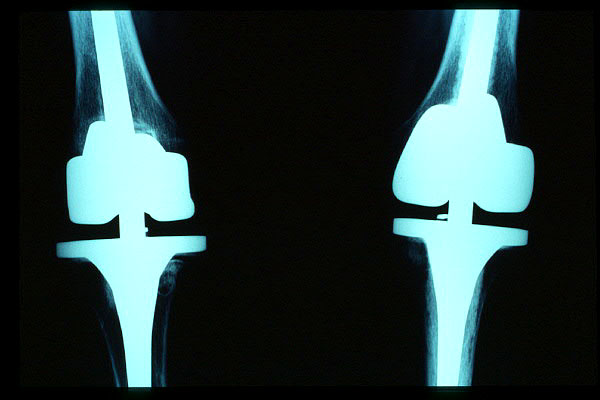

Prótesis completa bilateral de rodillas.